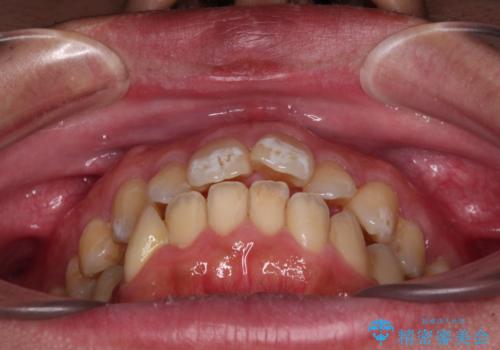

- 口が閉じられないとのことで来院された患者様です。

顎先に力を入れないと唇が閉じきれない口元であったので、上下左右の第一小臼歯4本を抜歯して、ワイヤー装置にて矯正治療を行うこととしました。